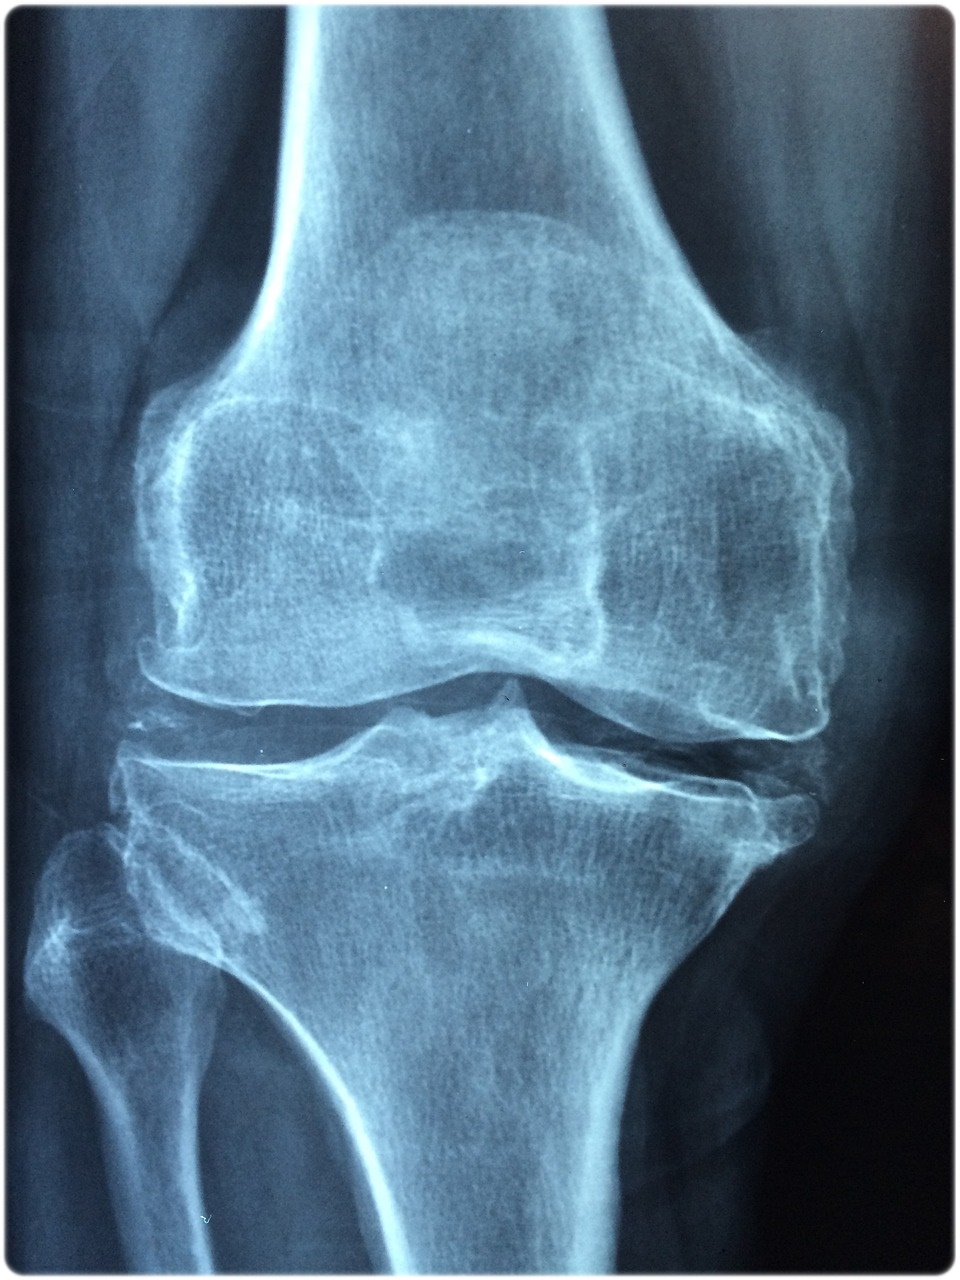

골다공증을 예방하고 조기에 관리하기 위해 가장 중요한 것은 골밀도 검사를 통한 정기적인 모니터링입니다. 골밀도 검사는 특히 중년 여성과 폐경 후 여성에게 필수적으로 권장되며, 뼈의 밀도와 구조를 파악하여 골다공증의 위험을 조기에 발견하고 평가하는 데 중요한 역할을 합니다. 골밀도 검사를 통해 뼈의 상태를 정밀히 파악하고, 전문의와 상의하여 개인에 맞는 예방 및 치료 계획을 수립하는 것이 필요합니다. 이러한 정기 검사는 뼈의 손상을 조기에 발견하고 필요한 치료를 적시에 시행하는 데 도움을 주므로, 골다공증의 예방과 관리에 큰 역할을 합니다.